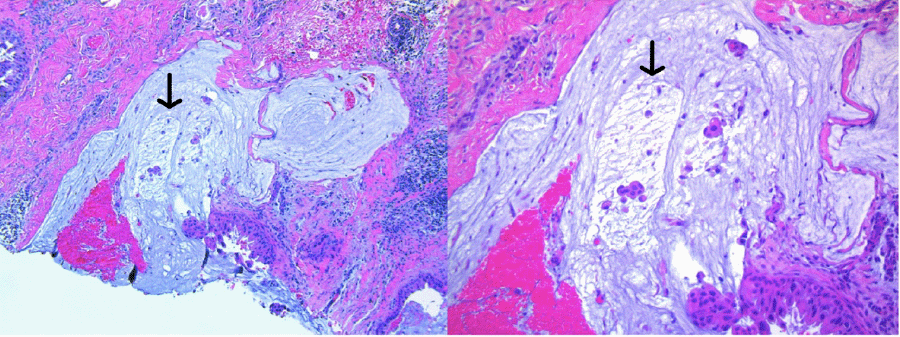

Given these findings, she was referred to a breast surgical oncologist for further evaluation. Ultrasound-guided core needle biopsy of the left breast mass revealed grade 1 invasive mucinous carcinoma, ER-positive (90%–95%), PR-positive (5%–10%), HER2-positive (3+ by IHC), and Ki-67 (20%–25%), with associated grade 2 ductal carcinoma in situ (Figure 4). Ultrasound-guided fine needle aspiration of two left axillary lymph nodes proved nondiagnostic in one node and negative for metastatic carcinoma in the second node. No evidence of metastatic disease was detected on PET imaging. Genetic testing was negative for any gene mutations, particularly GATA3, which is known to be one of the most frequently mutated genes in pMC. Given her clinical prognostic Stage IB T3 N0 M0 triple-positive left breast cancer, she was recommended primary systemic therapy with neoadjuvant chemotherapy. Thus, the patient underwent four cycles of intravenous doxorubicin and cyclophosphamide, followed by weekly paclitaxel for 12 weeks, as well as trastuzumab and pertuzumab every three weeks.

Figure 4. Pathology From Core Needle Biopsy. Published with Permission

Pure mucinous carcinoma 10x (left) and 20x (right)